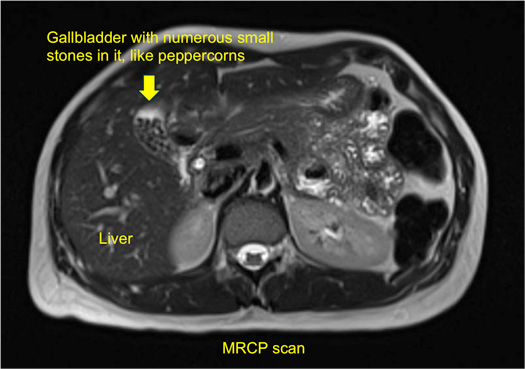

Occasionally, other tests may be required, such as an MRI scan (referred to as MR cholangio-pancreatography or MRCP), CT scan, or radio-isotope tests such as HIDA scans. An MRCP will show the anatomy of the liver and the gall bladder, the bile duct, as well the surrounding organs such as the pancreas (see illustration).

The gallbladder can develop just one or two large stones (some can be as large as a golf ball), or lots of tiny stones (as small as grains of sand).